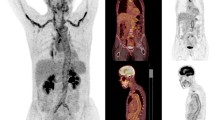

To estimate the diagnostic accuracy of conventional 18F-FDG PET/CT of cranial arteries in the diagnosis of giant cell arteritis (GCA).

The study was a retrospective case-control study. The reference diagnosis was fulfillment of the 1990 ACR criteria for GCA. All patients had new-onset GCA. Conventional 18F-FDG PET/CT was performed before glucocorticoid treatment. Controls were age- and sex-matched patients with a previous history of malignant melanoma (MM) undergoing surveillance PET/CT >6 months after MM resection. PET images were evenly cropped to include only head and neck and were assessed in random order by four nuclear medicine physicians blinded to reference diagnosis. Temporal (TA), maxillary (MA) and vertebral (VA) arteries were visually rated for 18F-FDG uptake. Interreader agreement was evaluated by Fleiss kappa.

A total of 44 patients and 44 controls were identified. In both groups, the mean age was 69 years (p = 0.45) and 25/44 were women. 35/41 GCA patients were temporal artery biopsy positive (TAB). Considering only FDG uptake in TA and/or MA, diagnostic sensitivity and specificity was 64 and 100%. Including VA, sensitivity increased to 82% and specificity remained 100%. Interreader agreement was 91% and Fleiss kappa 0.82 for the PET diagnosis based on the cranial arteries.

Conventional 18F-FDG PET/CT is an accurate and reliable tool to diagnose cranial arteritis in glucocorticoid-naïve GCA patients. The high diagnostic specificity suggests that TAB can be omitted in patients with 18F-FDG uptake in cranial arteries. 18F-FDG PET/CT performed in patients with suspected vasculitis should always include the head and neck.